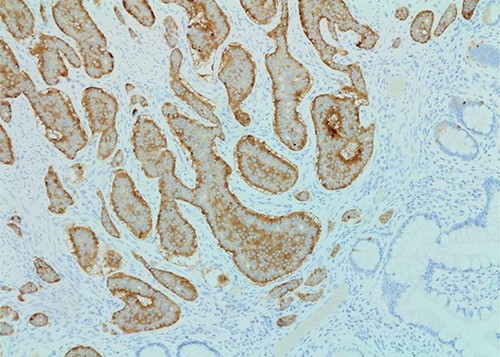

The patient was taken to the operating room for a laparoscopic appendectomy. During surgery, the appendix was noted to be gangrenous and perforated. Because the inflammation involved the entire appendix including the appendiceal base, decision was made to perform an ileocecectomy. Pathology revealed a gangrenous perforated appendix with periappendiceal abscess along with a well-differentiated, 1.2 cm neuroendocrine tumor of the terminal ileum (Figs 1 and 2). Mitotic index was 2.8 mitoses per 2 mm2, and Ki67 proliferative index was 3%. Five of nine lymph nodes were positive for metastatic neuroendocrine tumor with extranodal extension of the tumor and perineural invasion. Surgical margins were clear. Tumor, node and metastasis (TNM) histopathologic stage was pT2, N1. The patient developed a postoperative ileus but this resolved and she was discharged on postoperative day 7.

Synaptophysin stain (×100 magnification) of small bowel neuroendocrine tumor.